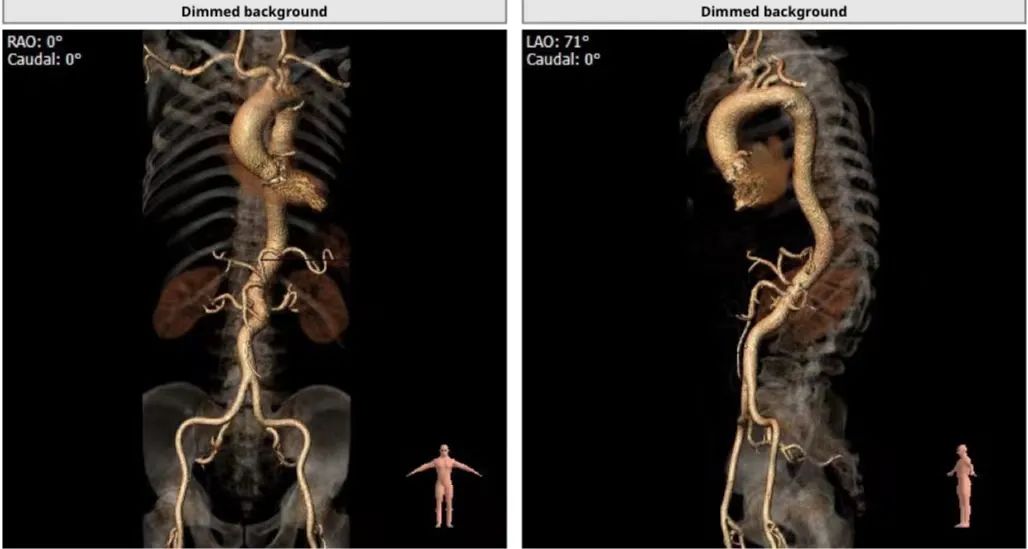

患者为功能型二叶瓣,瓣叶增厚,重度钙化,右无可见钙化融合,左无局部粘连,瓣环平面仍可见钙化,双冠脉高度尚可,瓣叶未见冗长,考虑冠脉风险较低,心脏角度约51°,考虑瓣环平均直径26.4mm,流出道平均直径24.8mm,短径为23mm,选择23球囊预扩,结合中国人群二叶瓣比例高,钙化重,故选择径向支撑力强的启明第三代可回收Venus-A Pro 29mm瓣膜。

入路选择: 主动脉弓降部走行呈直角,整体直径较大,但存在多处扭曲(胸主动脉+腹主动脉+双侧髂动脉-股动脉),综合考虑,荐右侧股动脉做为主入路。